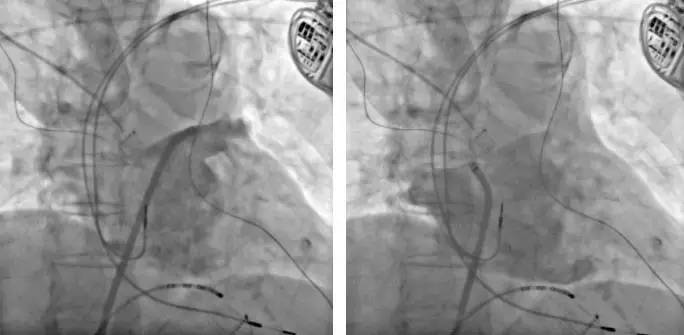

术中常规消毒铺巾,穿刺双侧股静脉,置入10极CS电极,穿刺房间隔并行LA-PV造影(图3),LA三维标测建模,行双侧环肺静脉消融及三尖瓣峡部消融,并实现阻滞,反复BURST刺激未能诱发心动过速(图4)。术中考虑高龄人群心肌纤维化增加,保持消融导管贴靠压力维持在10g左右,控制放电时间,以保证消融效果且防止过度消融,X线照射采用低剂量模式,监测血压/5分钟,专人随时与患者沟通,观察生命体征及特殊不适症状。手术过程顺利,双侧肺静脉前庭逐点消融后即实现隔离,避免了重复消融,整台手术历时90分钟。术后患者安返病房(图5:术后心电图)。

图3.LA-PV造影,左右两图分别为左、右肺静脉造影,同时可见双腔起搏器及电极。